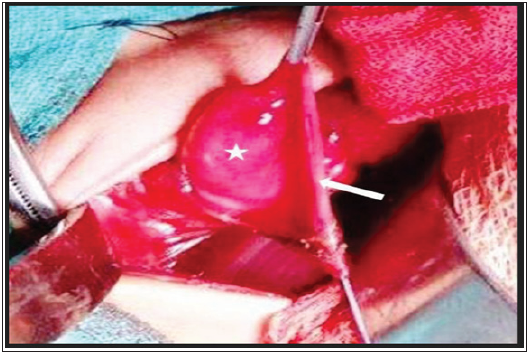

A two days old female baby, 1.2 kg birth weight, 35 week gestation, short for gestational age, referred to us with respiratory distress since birth. Baby had scaphoid abdomen. Chest X-ray showed bowel loops in left side of chest. Routine investigations were hemoglobin 15.7gm%, hematocrit 45.2%, total leucocyte counts 9600/cmm, platelets 80000/cmm. Venous blood gas showed pH 7.41, pO2 68, pCO232mmHg, HCO3 15.4 and rest of investigations were within normal limits. Baby underwent left subcostal exploration and had left CDH containing bowel, stomach, spleen, left upper pole of kidney, left adrenal gland and a large hernia sac. Upper lip of diaphragm was well formed. Lower lip was not formed laterally. At the time of excision of sac, a large nodule was identified sequestered on sac(Figure 1). The hernia sac along with the nodule was excised and defect was repaired by non-absorbable proline sutures. In post-operative period, baby had deranged INR of 3.0, platelet count 82000, urea 54, creatinine 2.1, Na+129, K+6.9 and developed pulmonary hemorrhage and succumbed to persistent pulmonary hypertension. Histopathology of nodule revealed sequestered lung tissue.

Figure 1: Intra-operative photograph showing a large nodule (white asterix) inside the hernia sac (white arrow).